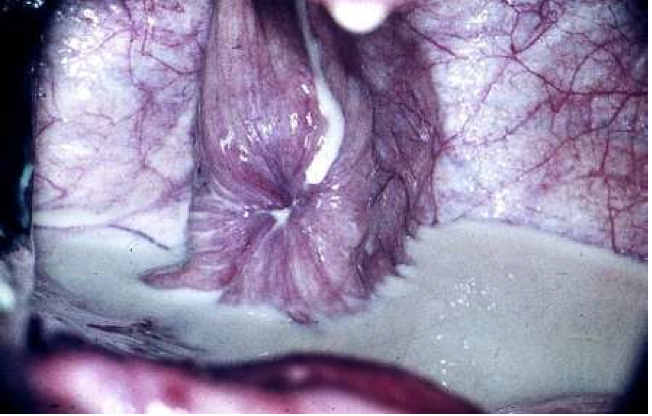

Fossa clitoridis

Sinus clitoridis